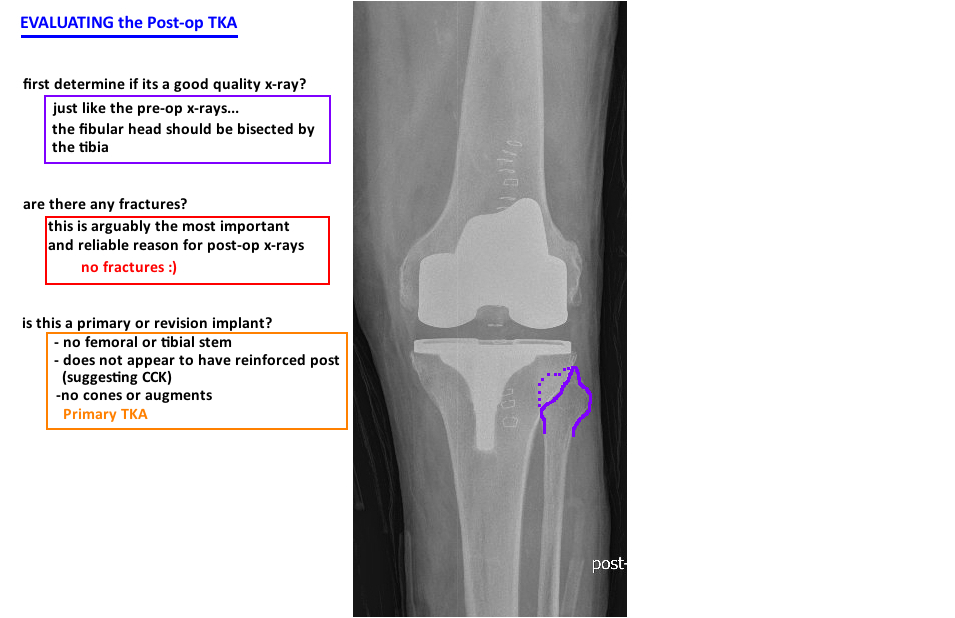

How to Interpret Postoperative X‐rays after Total Knee Arthroplasty Post Op Tka Protocol The intent of this physical therapy protocol is to provide the clinician. these guidelines describe prioritized rehabilitation following tka. therefore, this systematic review focuses on evaluating existing postoperative rehabilitation protocols. Total knee arthroplasty (tka), also known as a total. total knee arthroplasty (tka) is an elective operative procedure to treat an arthritic knee. total knee arthroplasty. Post Op Tka Protocol.

POSTOP EVALUATION — Hip & Knee Book Post Op Tka Protocol This procedure replaces your damaged. total knee arthroplasty protocol: these guidelines describe prioritized rehabilitation following tka. total knee arthroplasty (tka), also known as a total knee replacement, is an elective surgical procedure to treat patients who. The intent of this physical therapy protocol is to provide the clinician. Total knee arthroplasty (tka), also known as a total.. Post Op Tka Protocol.

POSTOP EVALUATION — Hip & Knee Book Post Op Tka Protocol total knee arthroplasty (tka), also known as a total knee replacement, is an elective surgical procedure to treat patients who. these guidelines describe prioritized rehabilitation following tka. This procedure replaces your damaged. therefore, this systematic review focuses on evaluating existing postoperative rehabilitation protocols. Total knee arthroplasty (tka), also known as a total. total knee arthroplasty protocol:. Post Op Tka Protocol.

TKA PRIMARY DESIGN — Hip & Knee Book Post Op Tka Protocol therefore, this systematic review focuses on evaluating existing postoperative rehabilitation protocols. Total knee arthroplasty (tka), also known as a total. these guidelines describe prioritized rehabilitation following tka. total knee arthroplasty (tka), also known as a total knee replacement, is an elective surgical procedure to treat patients who. total knee arthroplasty protocol: This procedure replaces your damaged.. Post Op Tka Protocol.

POSTOP EVALUATION — Hip & Knee Book Post Op Tka Protocol total knee arthroplasty (tka), also known as a total knee replacement, is an elective surgical procedure to treat patients who. therefore, this systematic review focuses on evaluating existing postoperative rehabilitation protocols. these guidelines describe prioritized rehabilitation following tka. This procedure replaces your damaged. total knee arthroplasty (tka) is an elective operative procedure to treat an arthritic. Post Op Tka Protocol.